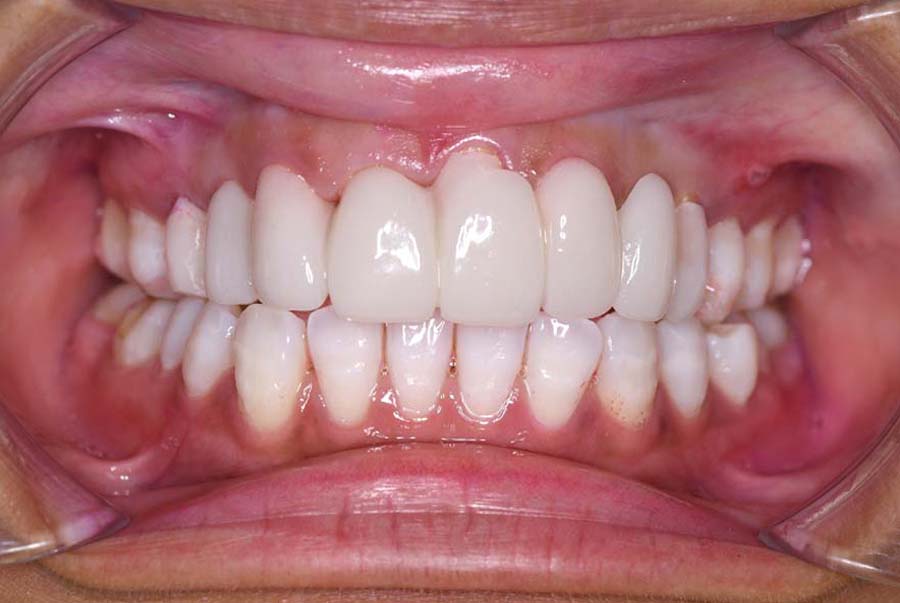

バイトアップ後

| 治療内容 | ①スプリントを装着 ②副子を装着 ③2024年4月 口腔内反映開始 ④副子を入れた状態の所まで咬合を挙上 (バイトアップ) ⑤2024年5月 上顎前歯部8本へ仮歯(TEK) を装着 |

2024年 10月 下顎MTM開始